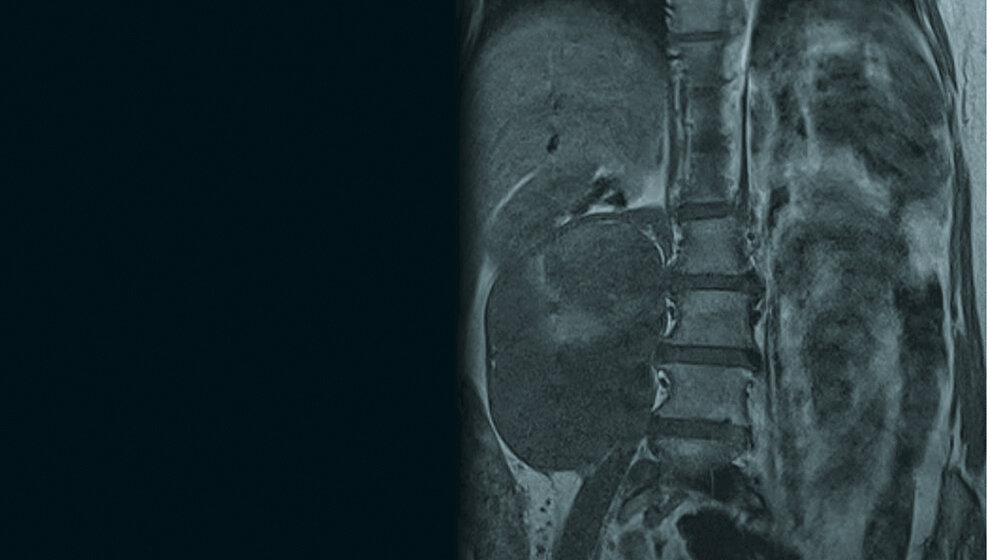

Das Liposarkom ist das häufigste Weichteilsarkom und macht etwa 20 % der Sarkome des Erwachsenen aus. Retroperitoneale Weichteilsarkome haben wegen ihrer speziellen Lage die Tendenz, über einen langen Zeitraum asymptomatisch zu sein und eine beachtliche Größe zu erreichen, bevor sie diagnostiziert werden. CT und MRT sind gute diagnostische Methoden. Die Chirurgie spielt die dominante Rolle in der Behandlung. Low-grade-Tumoren und makroskopisch tumorfreies OP-Gebiet sind signifikant mit einem reduzierten Rezidivrisiko und verbesserter Überlebenschance verbunden.